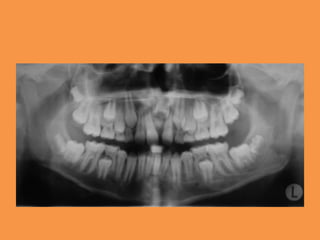

Figure 3: Panoramic radiograph

showing mild eruption of 11

Fig.2 Panoramic radiograph showing

impacted maxillary central

incisor and mesiodens in region of 21

Figure 3: Panoramicradiograph showing mild eruption of 11

• 29.

Fig.2 Panoramic radiographshowing impacted maxillary central incisor and mesiodens in region of 21